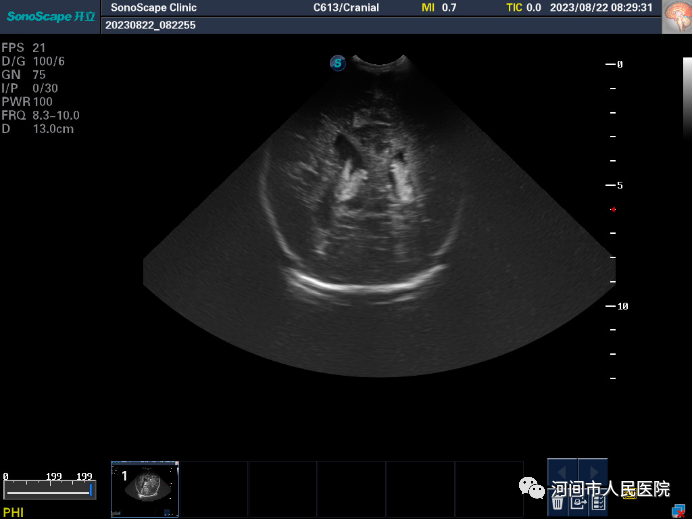

▲新生儿脑积水